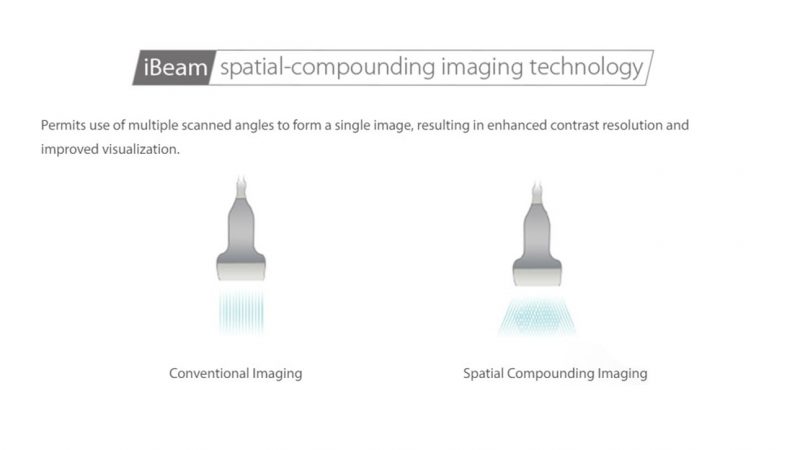

- iBeam, Permits the use of multiple scanned angles to form a single image, resulting in enhanced contrast resolution and improved visualization